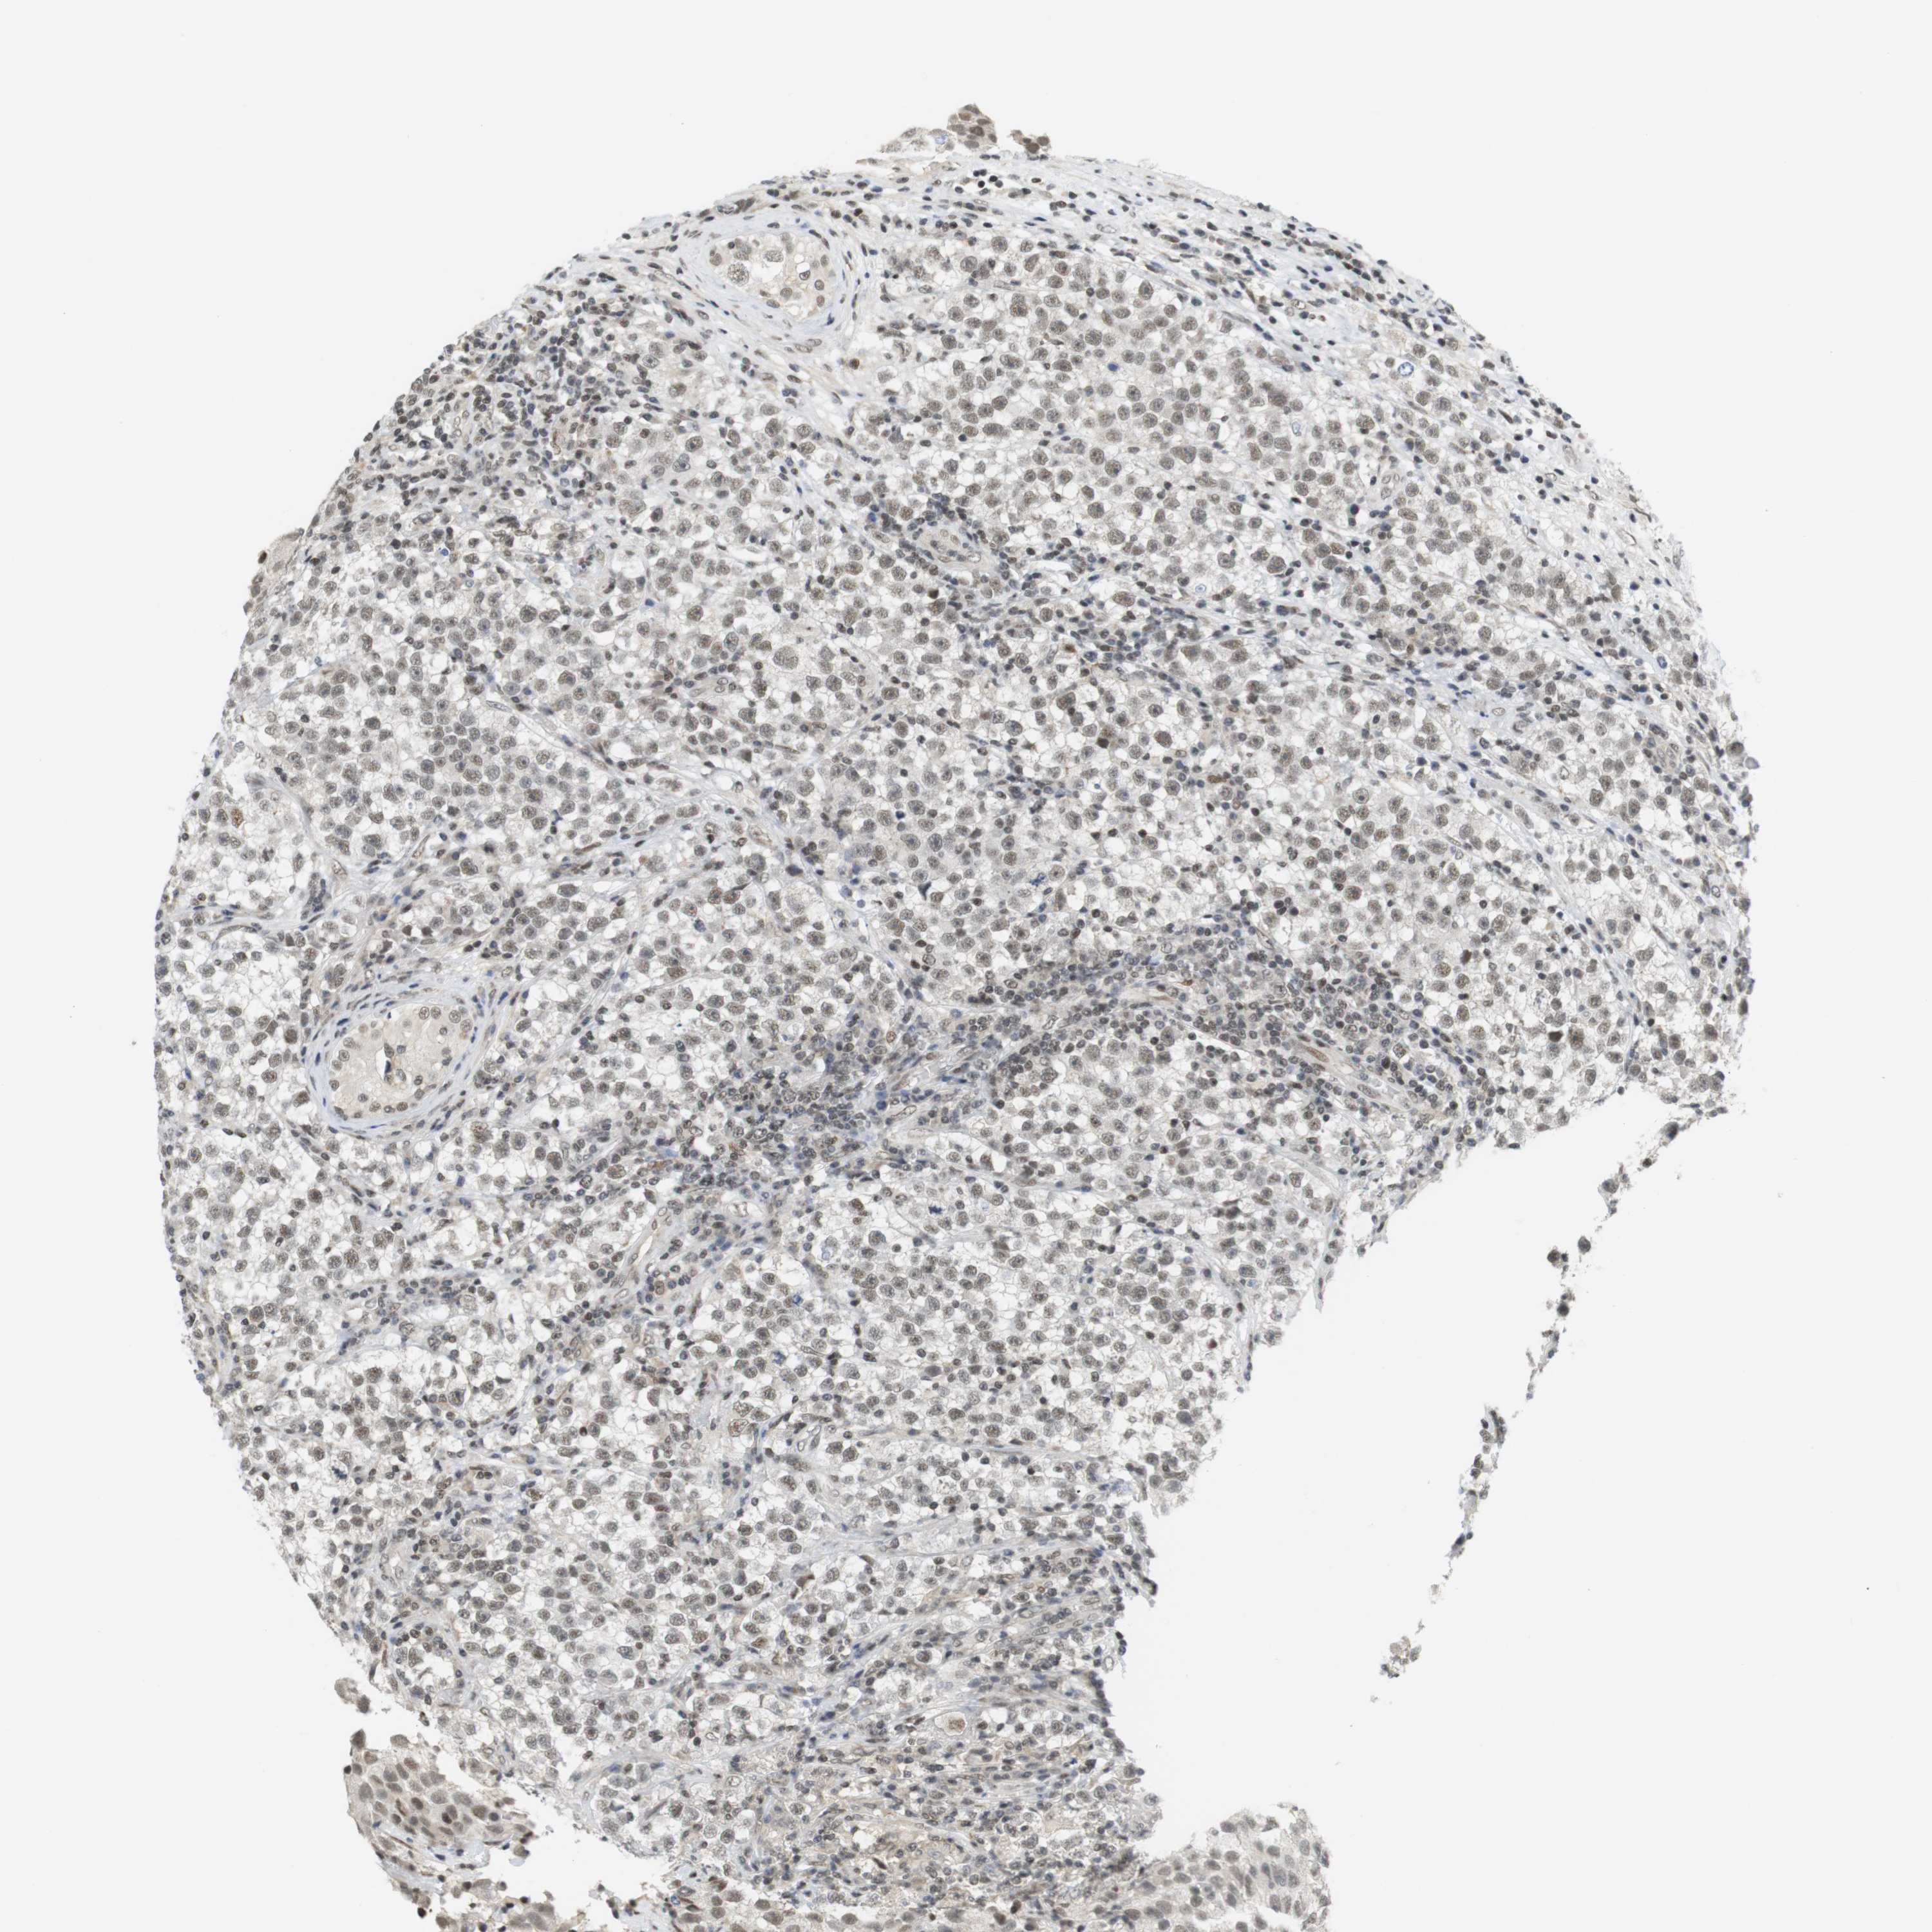

TESTIS CANCER - Protein expressioni

A mouse-over function shows sample information and annotation data. Click on an image to view it in a full screen mode. Samples can be filtered based on level of antibody staining by selecting one or several of the following categories: high, medium, low and not detected. The assay and annotation is described here.

Note that samples used for immunohistochemistry by the Human Protein Atlas do not correspond to samples in the TCGA dataset.

Antibody stainingi

Antibody staining in the annotated cell types in the current human tissue is reported as not detected, low, medium, or high, based on conventional immunohistochemistry profiling in selected tissues. This score is based on the combination of the staining intensity and fraction of stained cells.

Each image is clickable and will lead to virtual microscopy that enables deeper exploration of all samples and also displays staining intensity scores, fraction scores and subcellular localization as well as patient and tissue information for each sample.

Antibody HPA061646

Staining

High

Medium

Low

Not detected

Intensity

Strong

Moderate

Weak

Negative

Quantity

>75%

75%-25%

<25%

None

Location

Nuclear

Cytoplasmic/membranous

Cytoplasmic/membranous,nuclear

Seminoma, NOS

Carcinoma, Embryonal, NOS

Teratoma, malignant, NOS